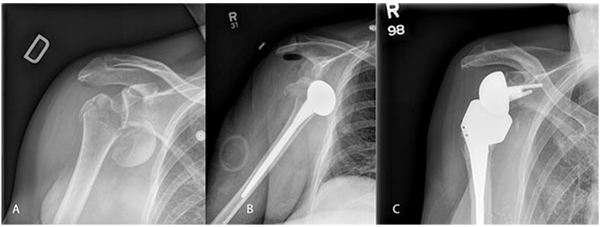

Fig. (1) A) plain xrays of comminuted acute proximal humerus fracture-dislocation. Note comminution of tuberosities and humeral head displacement with minimal calcar remaining. B) AP of post-operative day one humeral head replacement showing dislocation of prosthesis from glenoid. C) Six month post-operative follow-up AP imaging following revision to reverse total shoulder arthroplasty. Patient was doing functionally well with no complaints of pain and range of motion continuing to improve.